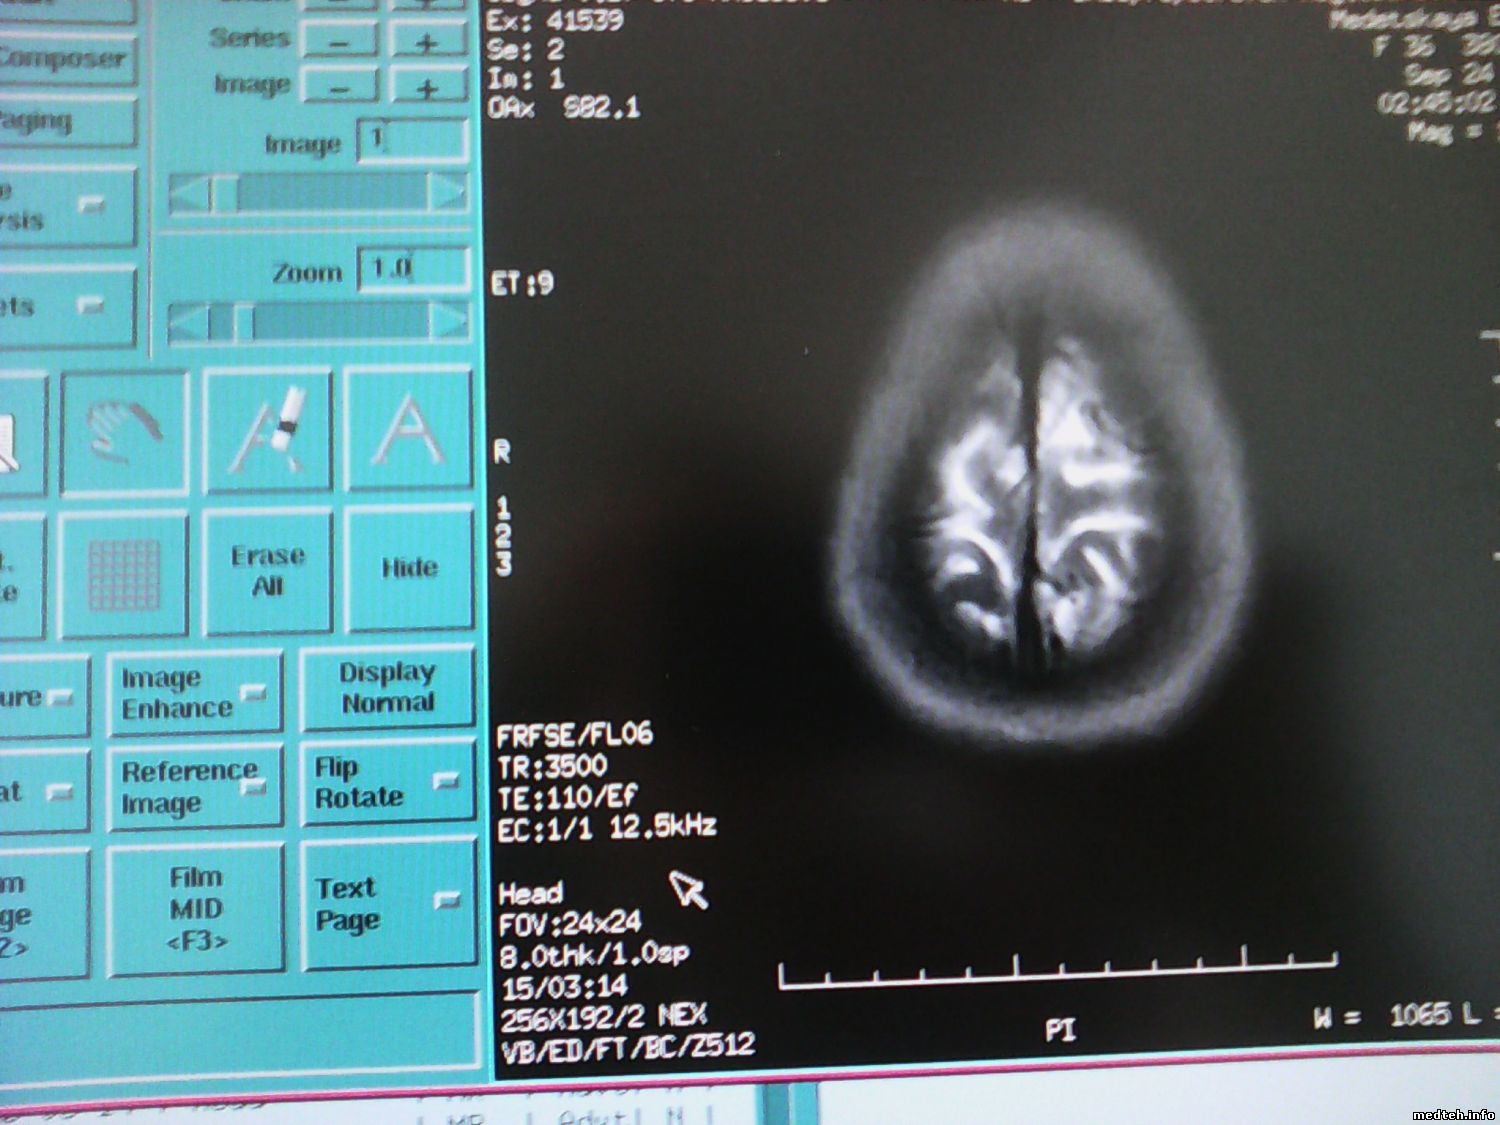

Посмотрел историю снимков, частота на снимках до поломки были 12,5 килогерц, сейчас 5,12 килогерц.

Manual Prescan - вообще показывает 4538978.jpg(88Kb) 6250 герц.

то чтоу вас на фото, 12.5 кГц это не частота аппарата, это параметр импульсной последовательности. Что бы на снимке посмотреть частоту надо нажать на кнопку "text info" она чуть левее 0164901.jpg(117Kb) на этом фото.

ФОТО сделал (1 фото)

то, что сейчас (2 фото)

1 фото, частота 8,553 - в диапазоне

2 фото, частота 8,425 - вне диапазона. Сканировать не будет